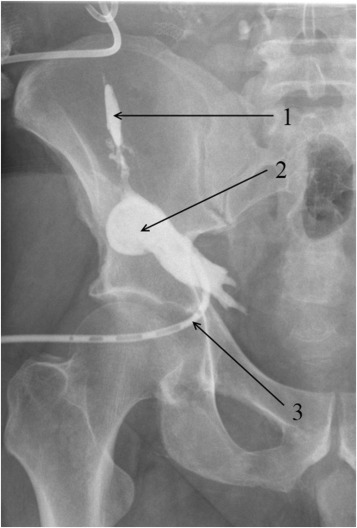

In one case, anastomotic dehiscence of the interduodenal anastomosis had caused the duodenal leakage with parapancreatic fluid collection formation in a female patient (Patient 25; Figure 2).

Gastrointestinal tract contrast X-ray radiography; (1) nasal-intestinal probe is ...

Gastrointestinal tract contrast X-ray radiography; (1) nasal-intestinal probe is inserted beyond the ligament of Treitz; (2) contrast-filled small-bowel loops; (3) contrast traveled into the drain through the interduodenal anastomosis dehiscence; (4) drain is inserted close to the vicinity of the interduodenal anastomosis; (5) visualized lines of staples sutures of the donor duodenum.

Transcutaneous drainage of the duodenal leak was performed under ultrasound and x-ray guidance. Prolonged drainage of the concerned area yielded a positive outcome. During fistulography, sufficient closing of the duodenal fenestration was confirmed. Following the fistulography, closure of the drainage canal was completed by using a blend of Type 1 human collagen with cancellous bone chips.